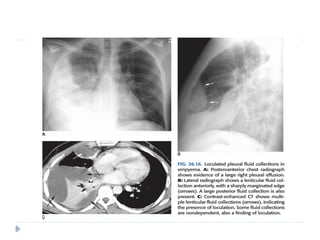

 Loculated effusion:

 Adhesions between the visceral and parietal

pleura result in development of loculated

collections along the inner aspect of the chest

wall.

 En face, they may appear as ill-defined round

opacities but tangentially they produce a

semicircular opacity whose margins form an

obtuse angle with the chest wall.

 This helps to distinguish them from peripheral

Atypical forms ofpleural effusion  Loculated effusion:  Adhesions between the visceral and parietal pleura result in development of loculated collections along the inner aspect of the chest wall.  En face, they may appear as ill-defined round opacities but tangentially they produce a semicircular opacity whose margins form an obtuse angle with the chest wall.  This helps to distinguish them from peripheral pulmonary tumors, which usually form an acute